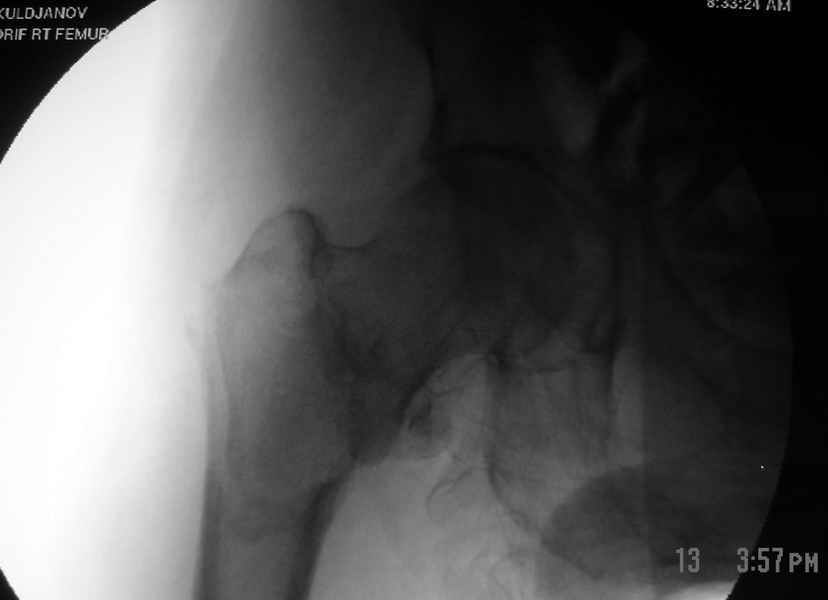

Как раз недавно у меня был примерный случай: больному 36 лет, поступил ночью, травма в результате мотоциклетной аварии, кроме чрезвертельного и спирального перелома левого бедра имеется переломы костей предплечья с этой же стороны. Скелетное вытяжение, а на следующий день больной про оперирован на ортопедическом столе с дистракцией. Чтобы не расколоть чрезвертельный перелом провели временную спицу ближе к переднему кортексу, из малого разреза костодержатель для репозиции, а фиксацию провели антиградным штифтом. Этапы операции на снимках.